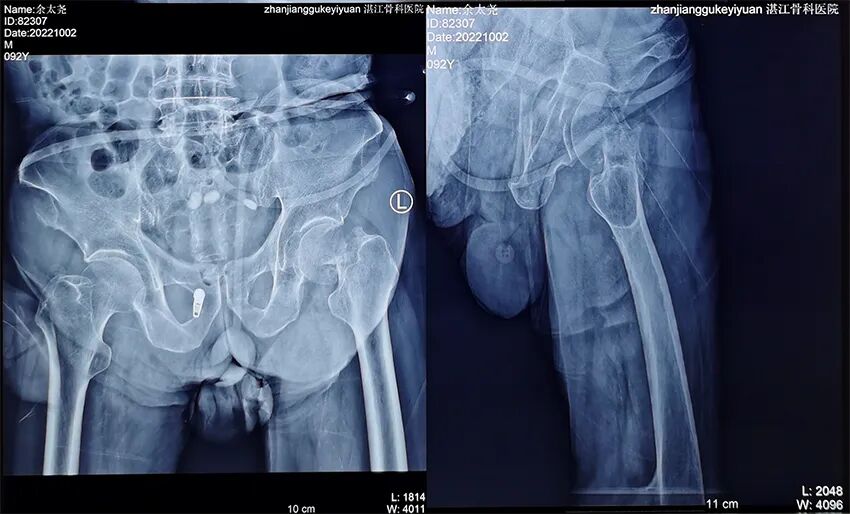

患者余某,男性,今年92岁,家住雷州纪家镇某村。

入院:2022年10月2日;出院:2022年10月19日。

术前图像